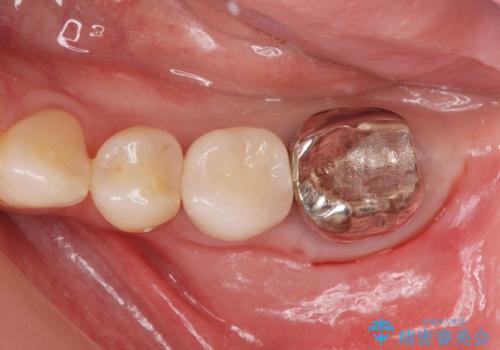

- 銀の詰め物が取れたとのことで来院。

詰め物の下には虫歯がありました。

白い物で治療して欲しいとのことで、セラミックの詰め物だと詰め物の範囲が大きく、割れてしまう可能性があるので

ジルコニアクラウン(被せもの)で治療を行いました。

銀の詰め物はかなり昔に治療されたそうです。

銀の詰め物は虫歯の再発リスクが高く、歯に痛みが出てしまうと歯の神経の治療もしないとならなくなってしまいます。